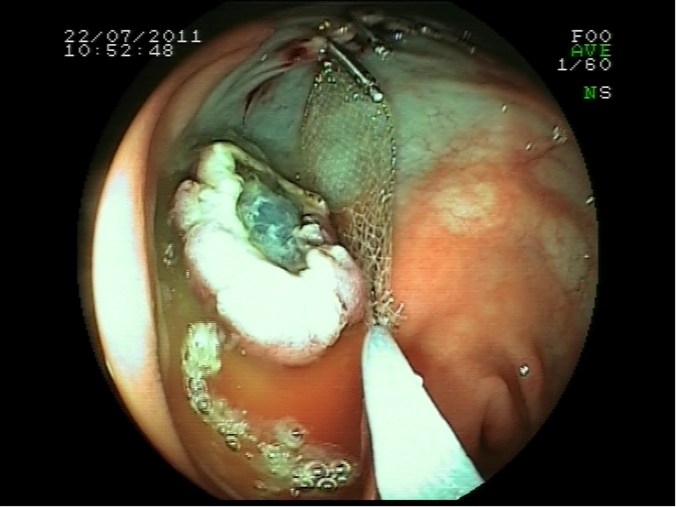

Retirada de pólipo con cesta